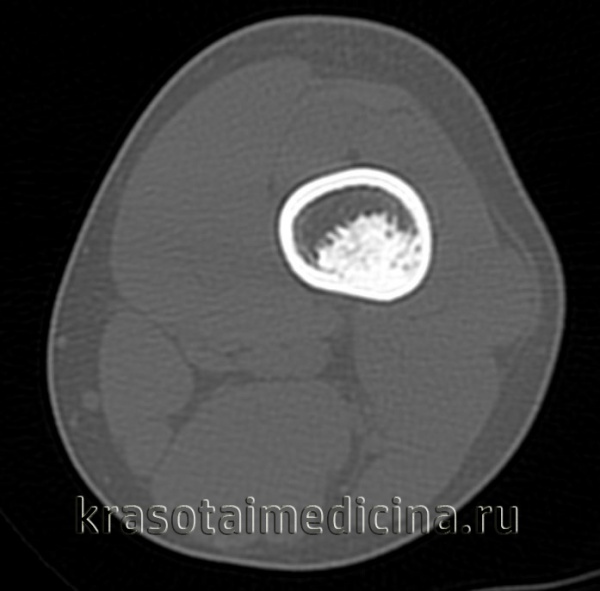

- Рентгенография кости. На снимках визуализируется кистообразные изменения или неоплазия в виде «мыльных пузырей» в метафизарной зоне. Признаки общего остеопороза отсутствуют, вокруг измененного участка может просматриваться остеосклероз. Границы доброкачественной ГКО более четкие, но из-за местно-агрессивного роста при значительном размере возможно появление «костного козырька». Выраженная периостальная реакция нехарактерна. Злокачественная остеокластома имеет нечеткую структуру. На снимках рано обнаруживается разрушение кортикального слоя.

- КТ и МРТ кости. Компьютерная томография дает более четкое представление о форме, размерах, границах гигантоклеточной опухоли, в сомнительных случаях позволяет подтвердить или опровергнуть разрыв коркового слоя. В ходе магнитно-резонансной томографии исследуют интрамедуллярный и кистозный компоненты, оценивают состояние окружающих мягких тканей, расположение сосудов и нервов. Методики помогают выбрать оптимальный вариант хирургического вмешательства, спланировать операцию.